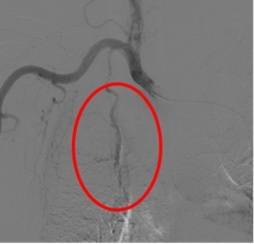

面对如此危重的病情,血管与介入科团队首先给吴女士进行了多组止血药的输注,但咯血依旧越来越重。经过缜密的病情分析和术前准备,唐俊和主治医师王成志于11月10日为吴女士进行了咯血动脉栓塞术。术中,医生熟练地将导管、导丝穿刺股动脉进入,通过造影找到出血病灶,利用弹簧圈+明胶海绵颗粒进行栓塞出血的肿瘤供血血管,从而达到止血目的。

除了堵住动脉的“漏洞”,医生还“顺便”给肿瘤“断粮”。术中,唐俊主任及其团队发现吴女士右侧支气管动脉和右侧胸廓内动脉异常发达,血流量增多,且参与肿瘤供血,遂果断对多支血管进行了栓塞,断了肿瘤部分供血。

右侧支气管动脉(肿瘤供血)栓塞后消失

右侧胸廓内动脉(肿瘤供血)栓塞后消失